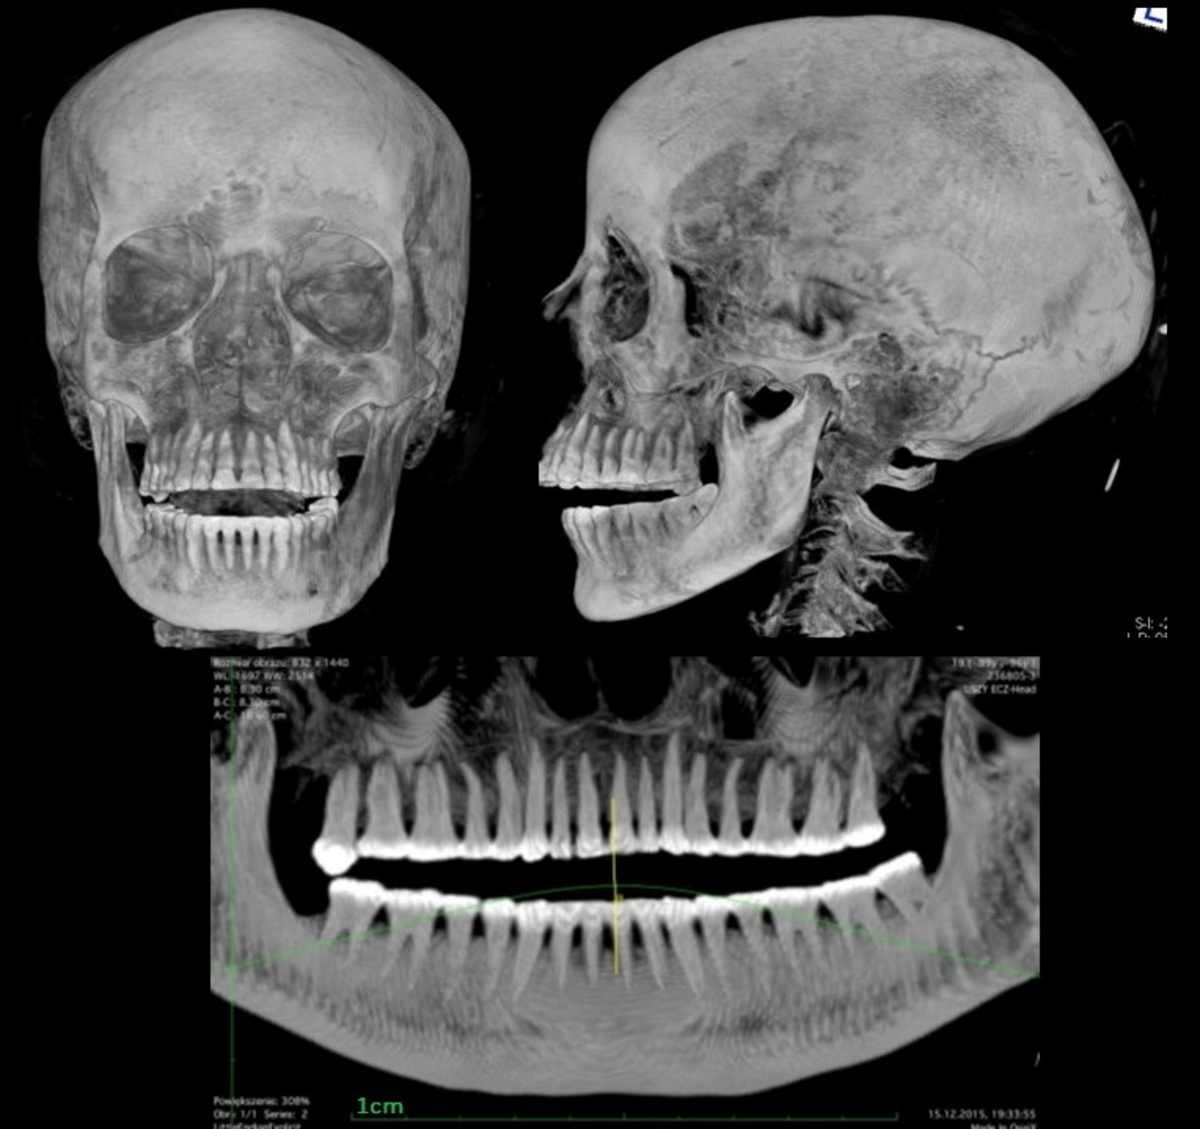

Marzena Ozarek-Szilke, an anthropologist at the Warsaw Mummy Project, was examining a CT scan of a mummy at the National Museum in the Polish capital when she spotted something peculiar.

"When I looked at the lesser pelvis of our mummy I was interested in what was inside... I thought I saw a tiny foot," Ozarek-Szilke said.

However, in a discovery revealed in the Journal of Archaeological Science on Thursday, scientists at the Warsaw Mummy Project said the mummy was in fact a woman in her twenties who was between 26 and 28 weeks pregnant.